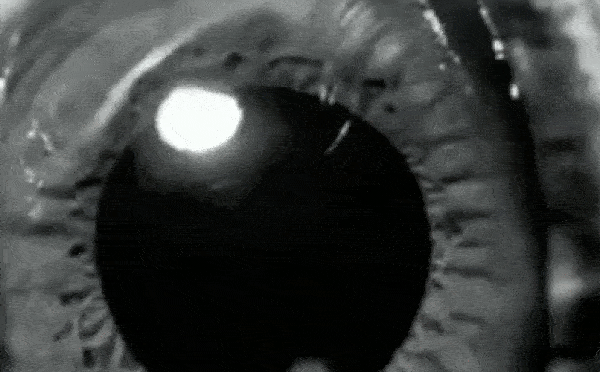

Sự giăn nở và co lại của đồng tử là những quá tŕnh hoàn toàn tự động. Do nhiều yếu tố khác nhau kích hoạt. Ví dụ như bước vào môi trường sáng hoặc tối, nhưng một nghiên cứu điển h́nh gần đây cho thấy không phải lúc nào cũng vậy.

Một sinh viên trẻ ở Đức có thể tự điều khiển các cơ nhỏ bé điều chỉnh kích thước của đồng tử, một kỳ tích mà trước đây các nhà khoa học cho là không thể xảy ra.

Các nhà nghiên cứu chỉ ra rằng một số người có thể thay đổi kích thước đồng tử của họ thông qua "phương pháp gián tiếp", tuy nhiên, người đàn ông trẻ này có thể điều khiển trực tiếp cơ ṿng trong mắt để điều chỉnh kích thước của đồng tử.

Trong suốt giai đoạn thử nghiệm, các nhà nghiên cứu không t́m thấy dấu hiệu nào cho thấy DW đang điều chỉnh kích thước đồng tử một cách gián tiếp. Bằng cách kiểm soát trực tiếp cơ mắt của ḿnh, người đàn ông này có thể giăn đồng tử có đường kính lên tới 2,4 mm và thu hẹp chúng xuống 0,88 mm.

Chàng trai trẻ thậm chí c̣n có thể co đồng tử của ḿnh vượt quá mức tối đa thường quan sát được khi tập trung vào các vật thể gần. Anh ấy nh́n rơ các vật thể gần khuôn mặt hơn gần hai lần so với khả năng b́nh thường khi không cần kiểm soát đồng tử.